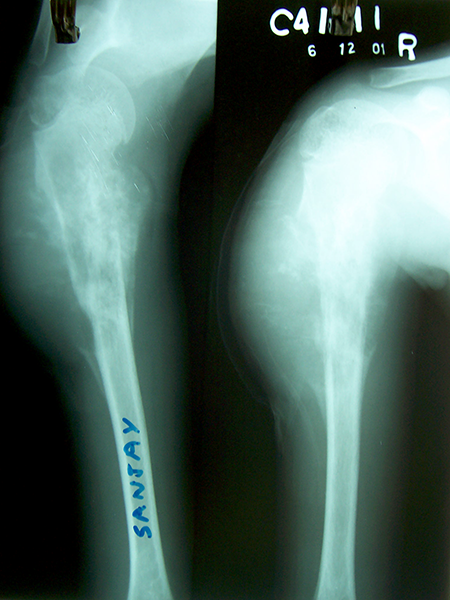

Case:3 Ewings Tibia

Pre-Op